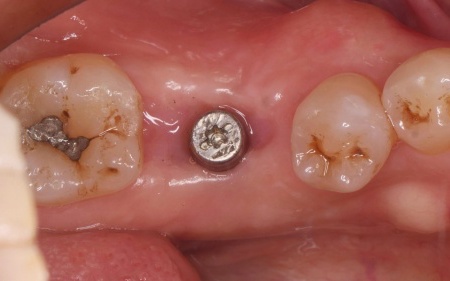

60代男性 歯が抜けている部位にインプラント治療を施した症例

拝見したところ、左下奥歯(第1大臼歯)が抜けており、見た目が気になるだけでなく奥歯でしっかりと噛むことが難しくなっていました。

①左下奥歯の欠損部位にインプラント埋入手術を実施。インプラントを正しい位置と角度であごの骨に埋入し、傷の治りを待つ

②インプラントがあごの骨に問題なく定着したことを確認したあと、インプラントの上に人工歯を装着する